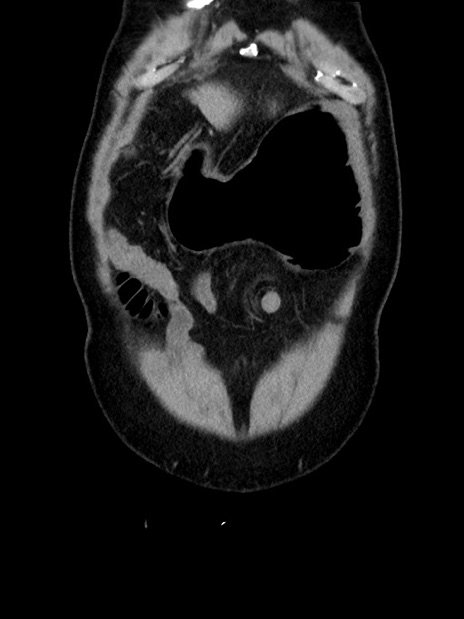

症例35(冠状断像)

横断像